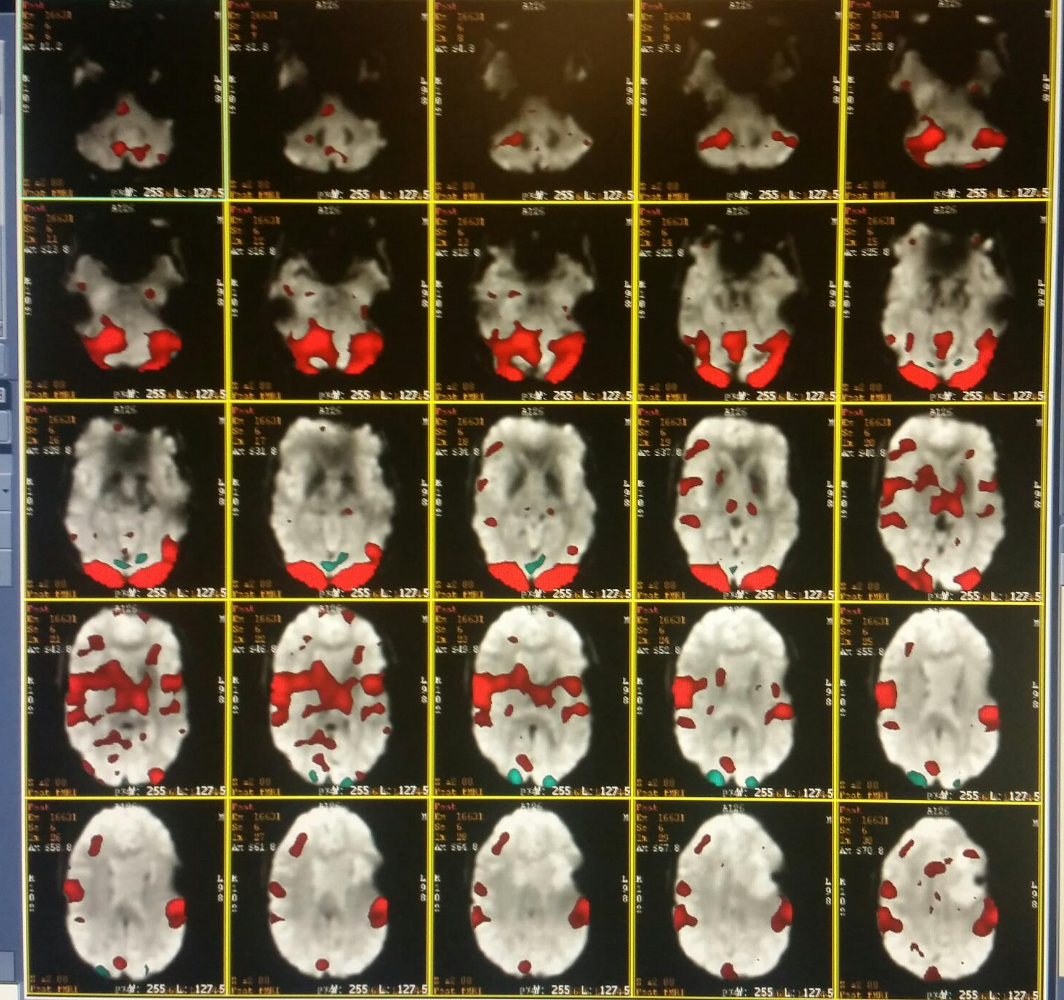

This time there would be no IV. This FMRI lasted about 90 minutes and the purpose is to identify speech and movement areas of my brain. Functional MRI works on something about iron and oxygen in your blood that allows them to study different areas of the brain. I trust it but couldn't explain it to anyone.

This will allow the surgeon to remove as much of the tumor as possible without (hopefully) impacting any of these areas. Looking at a screen that flashes, "move your right hand" for 5 seconds, then "relax". I went through this process for about 25 times for each hand, being shown an object and thinking of the name, being shown an object, listening to someone describe it and then thinking of the answer and finally moving my tongue. This was the most challenging MRI by far.

I've shared my normal brain scan before. This is my brain when I move my hands, move my tongue and listen to and think of names of objects.

Crazy huh?